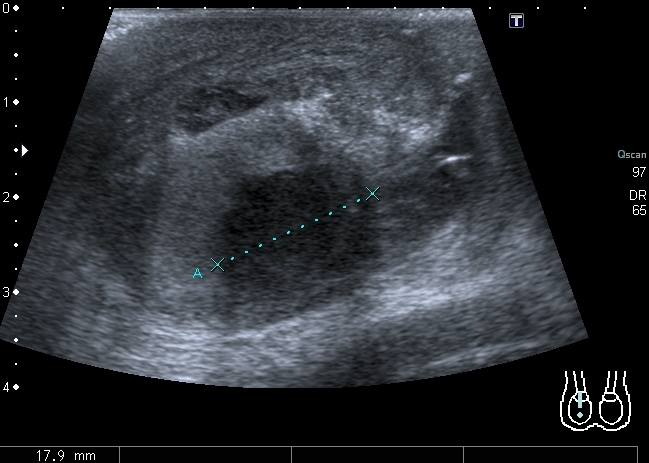

Сегодня смотрел его на контрольном УЗИ: в правой половине мошонки - небольшое количество жидкости. Яичко прежних размеров, кровоток в яичке востановился, но определяется в основном в подоболочечной зонеВ области ворот яичка - гипоэхогенный участок с нечёткими контурами. Вопрос: что делать дальше

Поговорил с хирургами, они считают, что это действительно участок некроза, но поскольку кровоток востановился, яичко оставили. В дальнейшем участок некроза, скорее всего заместится соединительной тканью. Будем надеяться, что так и будетKapustinSV писал(а):Видимо, участок некроза.